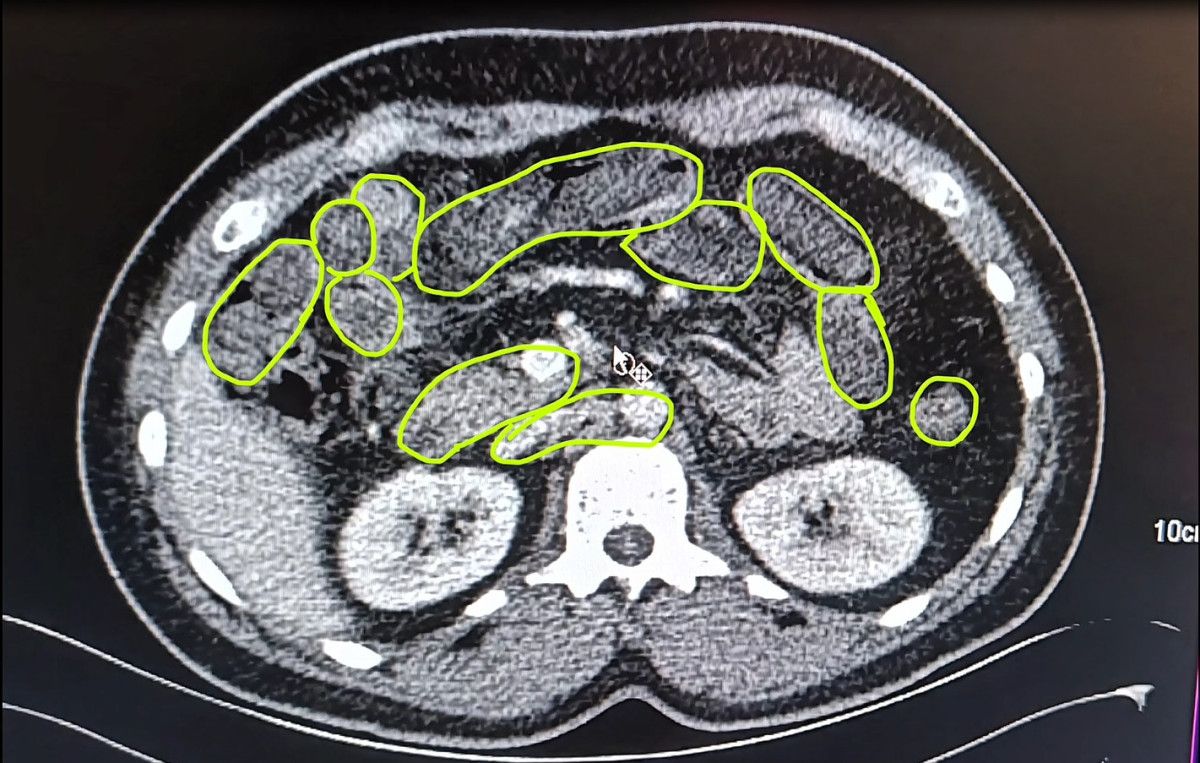

Kayseri Vilayet Jandarma Komutanlığı grupları Kocasinan ilçesi Himmetdede Mahallesi’nde İran asıllı 3 şüphelinin bulunduğu ticari aracı durdurdu.

Araçtaki A.O. (51), M.S. (37) ve P.S.’nin (28) üzerinde yapılan aramada bir ölçü uyuşturucu bulundu.

Zanlıların uyuşturucu unsurları yutmuş olabileceğini kıymetlendiren gruplar bu bireyleri hastaneye götürdü.

MİDELERİNDEN UYUŞTURUCU ÇIKTI

Röntgenlerinde midelerinde uyuşturucu unsur olduğu belirlenen zanlılardan 20 gram çeşitli uyuşturucu unsur ile 117 uyuşturucu hap ele geçirildi.